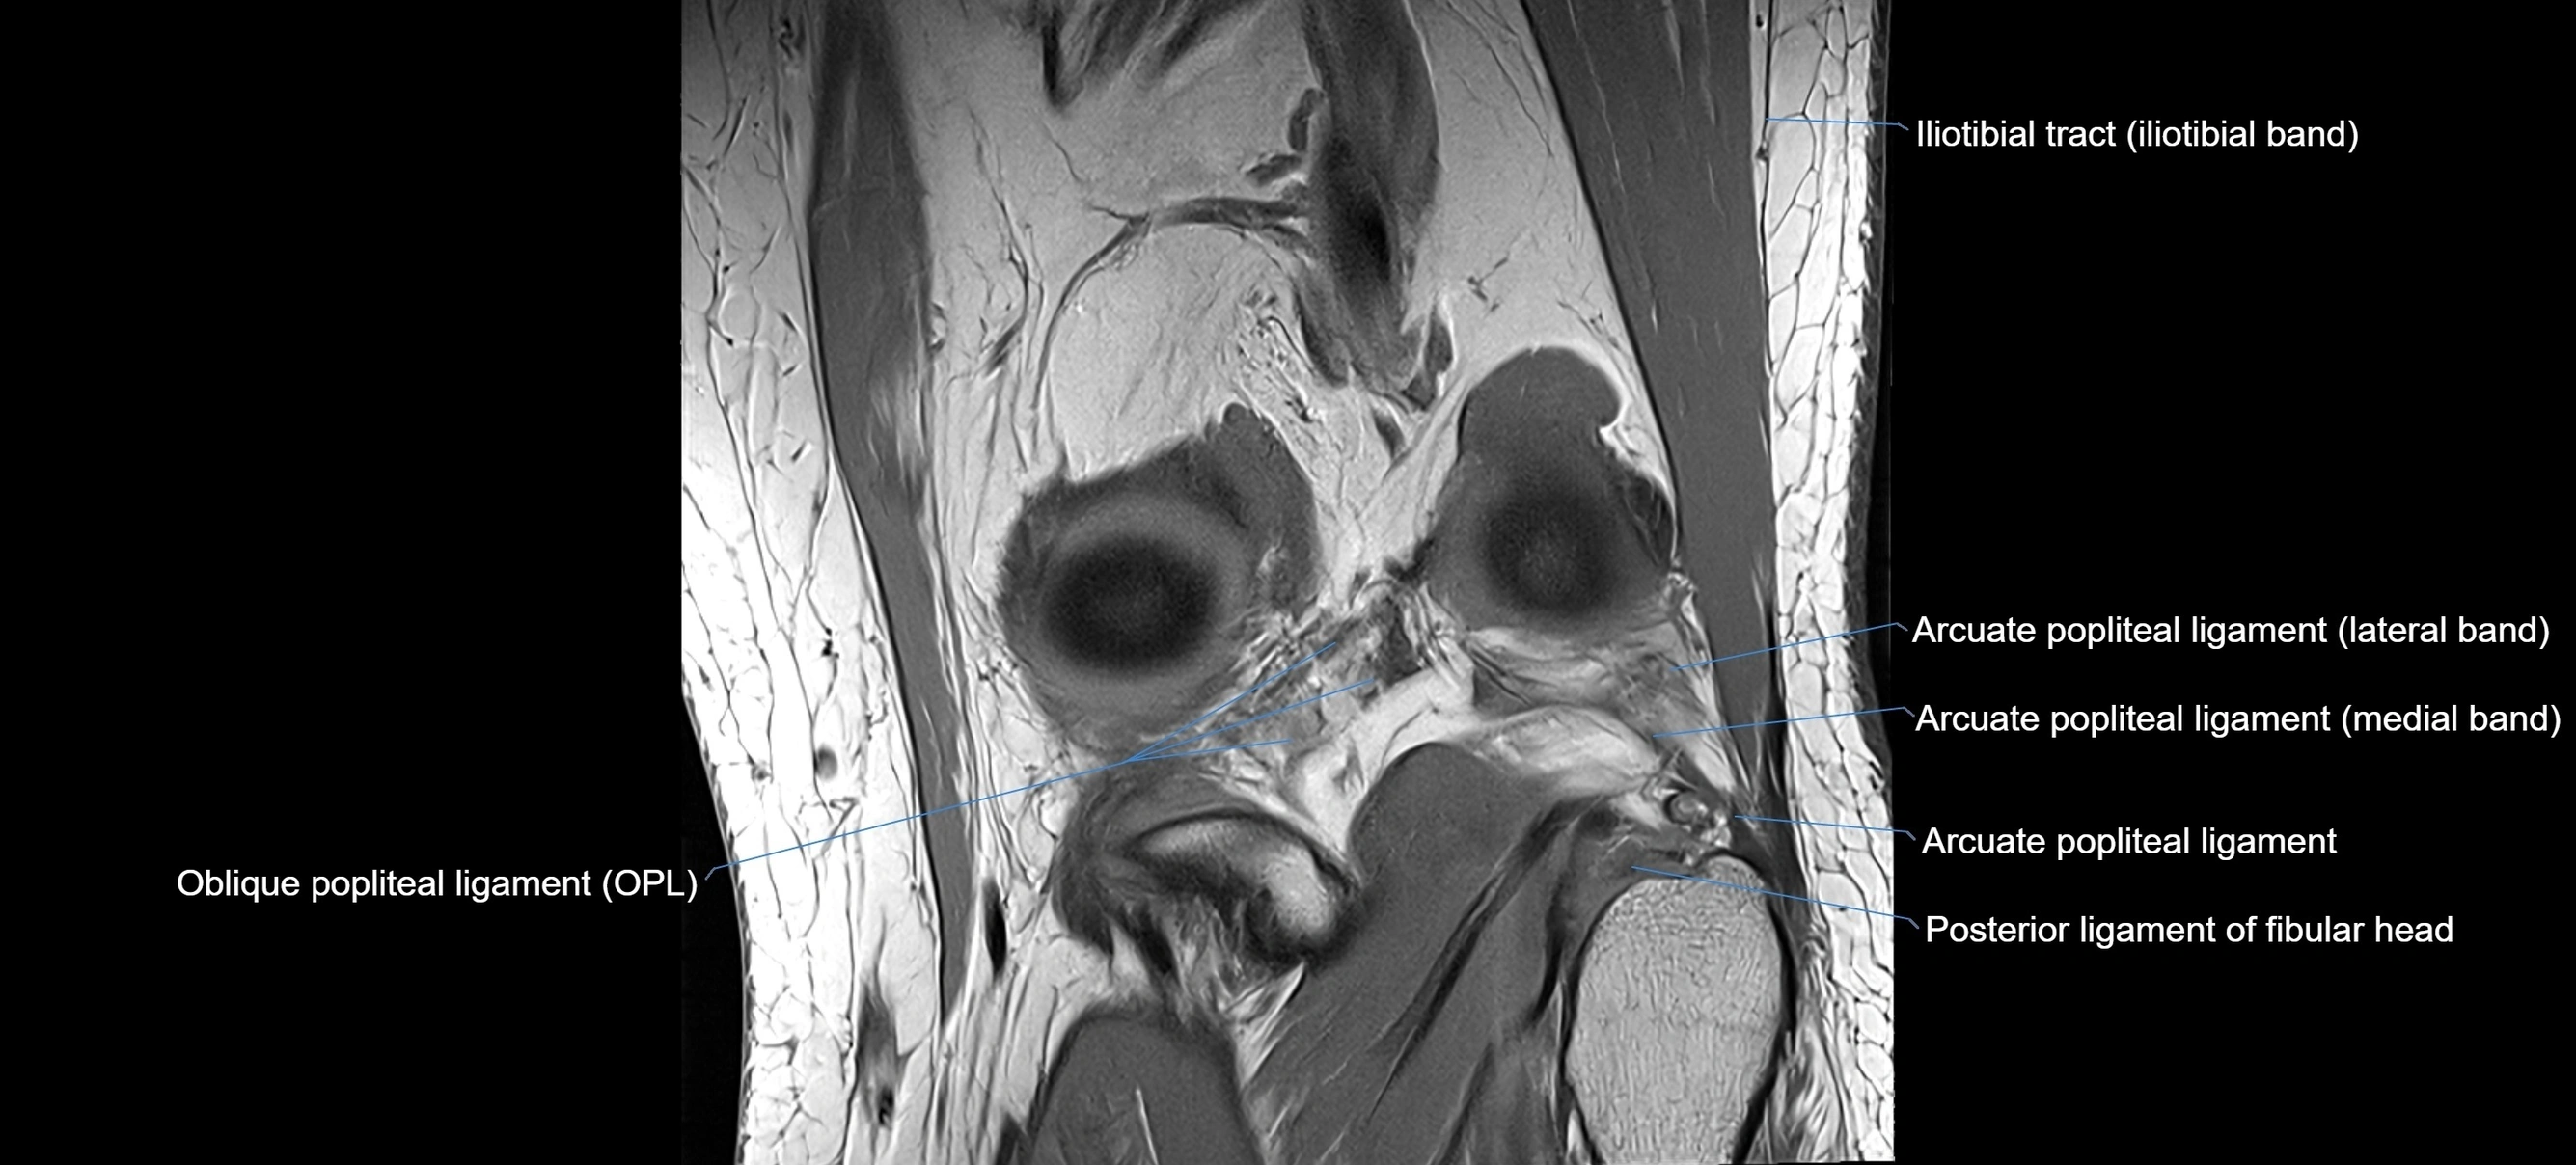

MRI images

image